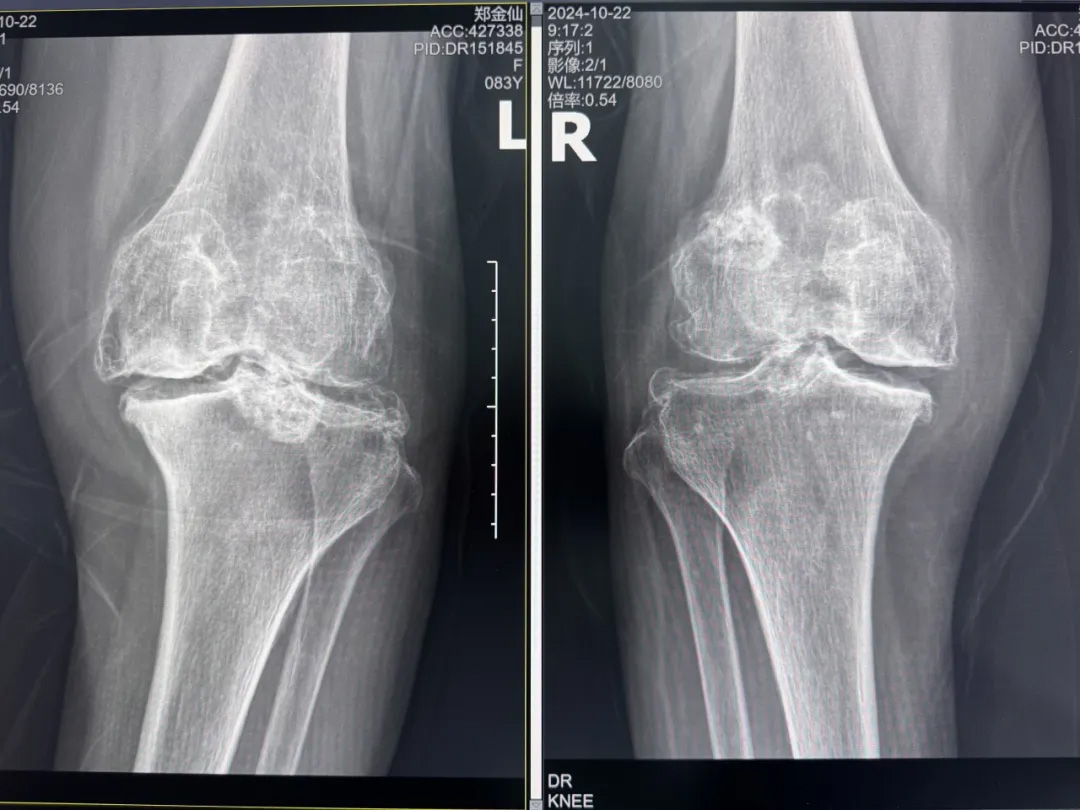

年輕時愛到處走走的鄭阿婆,晚年卻被雙膝劇痛困在輪椅上長達(dá)二十年。經(jīng)羅副院長診斷,她的膝關(guān)節(jié)軟骨幾乎磨光,關(guān)節(jié)嚴(yán)重畸形,呈"羅圈腿",走幾步便疼痛鉆心,連如廁都需家人抱扶。“我這輩子啊,估計再也站不起來了。”是阿婆最常說的話。

圖片